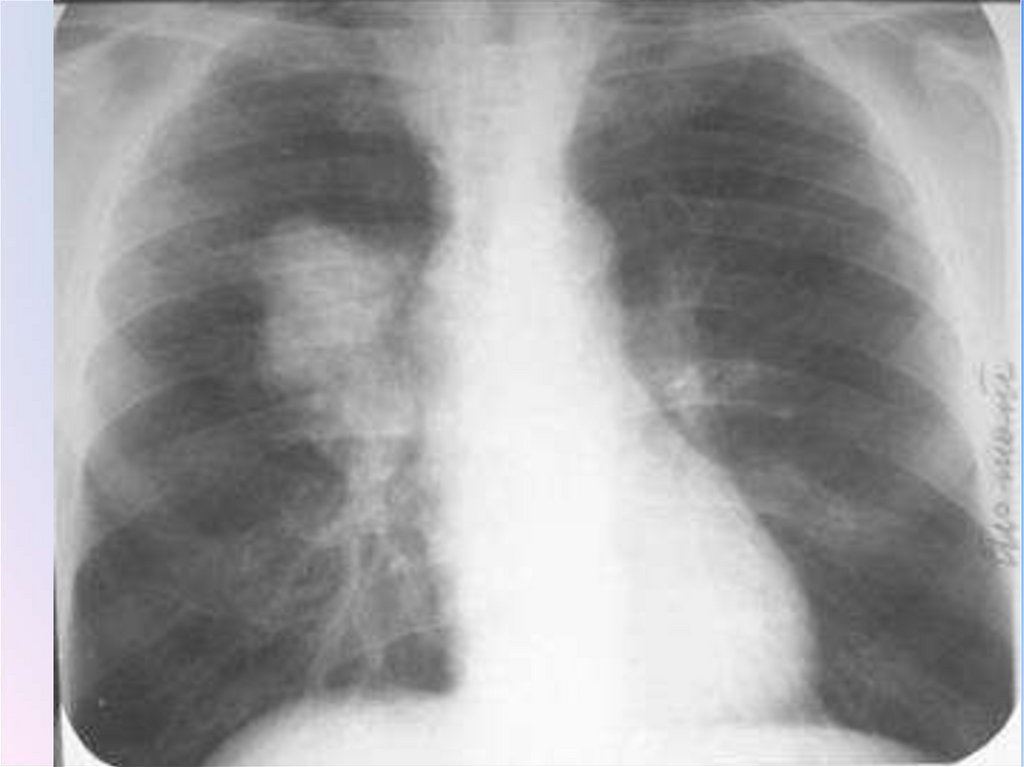

• В плане диф.диагностики следует подчеркнуть,

что плохо поддающаяся лечению пневмония

может оказаться туберкулезом легких или быть

маской онкологических (бронхогенный или

бронхоальвеолярный рак, лимфома) или

иммунологических(васкулиты, альвеолиты,

эозинофильная пневмония, альвеолярный

протеиноз) заболеваний, а также сердечнососудистой патологии – застойной сердечной

недостаточности и тромбоэмболии легочной

артерии